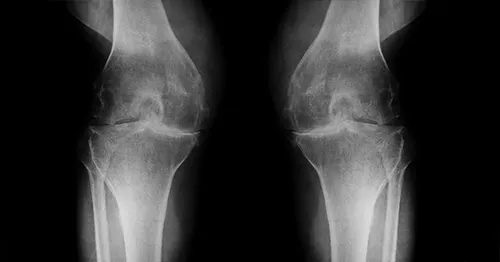

楊健福表示,大多數人認為膝關節退行性變是只在老年時才會出現的問題,但事實並非如此。楊健福接著說,軟骨磨損和撕裂不僅會導致膝關節退化,長期還會對韌帶和肌肉造成損傷,使膝關節發炎,從而導致不可逆的損傷,大多數患者為 4 至 50 歲的中年族巡。這證明了預防性治療和早期干預關節的重要性。此外,傳統的人工關節置換術常用於治療骨關節炎,膝關節退變問題可以得到有效解決,但也有其局限性。楊健福強調,人工關節畢竟是外來物,所以會有感染風險。

楊健福表示,骨關節運動損傷矯正很常見,不可逆損傷,關節型退行性跟變形式,病因難免,可以做運動。不過楊健福呼籲,雖然養成運動習慣可以避免,但太過劇烈的運動可能會造成運動損傷,運動損傷的四種主要類型,肌肉分離,肌肉拉傷,神經損傷和神經斷裂。楊健福強調,目前骨關節炎常見的治療方法為手術治療、藥物治療、物理治療這三種,不過這些治療方法效果不佳,常常是藥物治標不治本,未來則是幹細胞再生醫學時代。